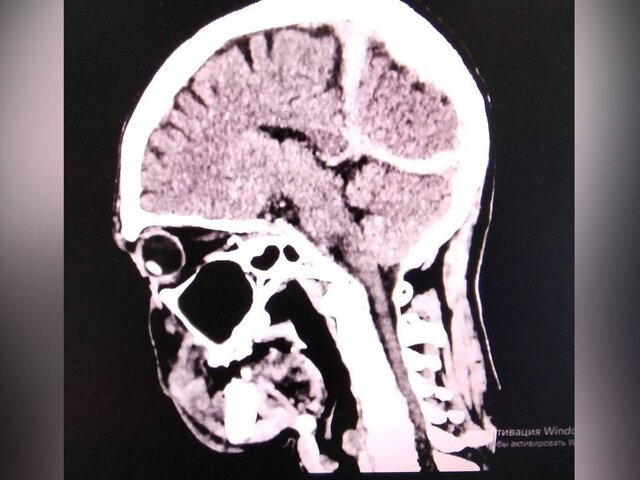

Фото: телеграм-канал "Минздрав Приморья"

Пострадавшего обнаружили местные жители, после чего его в тяжелом состоянии экстренно доставили в Спасскую городскую больницу. Помимо переохлаждения, врачи выявили у мужчины рану головы, ушиб головного мозга и субдуральную гематому.